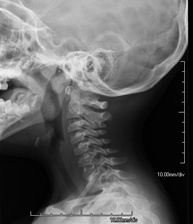

- Cervical spine X-ray

This technique uses X-ray rendered imaging for examining the cervical spine. Indicated for: trauma, cervical pain.

Técnica mediante la cual, utilizando rayos X, se obtienen imágenes del cavum para su estudio. Indicaciones: dificultad respiratoria, anginas de repetición en lactantes y niños. - RX Columna cervical

Técnica mediante la cual, utilizando rayos X, se obtienen imágenes de la columna cervical para su estudio. Indicaciones: traumatismo, contractura cervical, dolor articular. - RX Huesos propios nasales